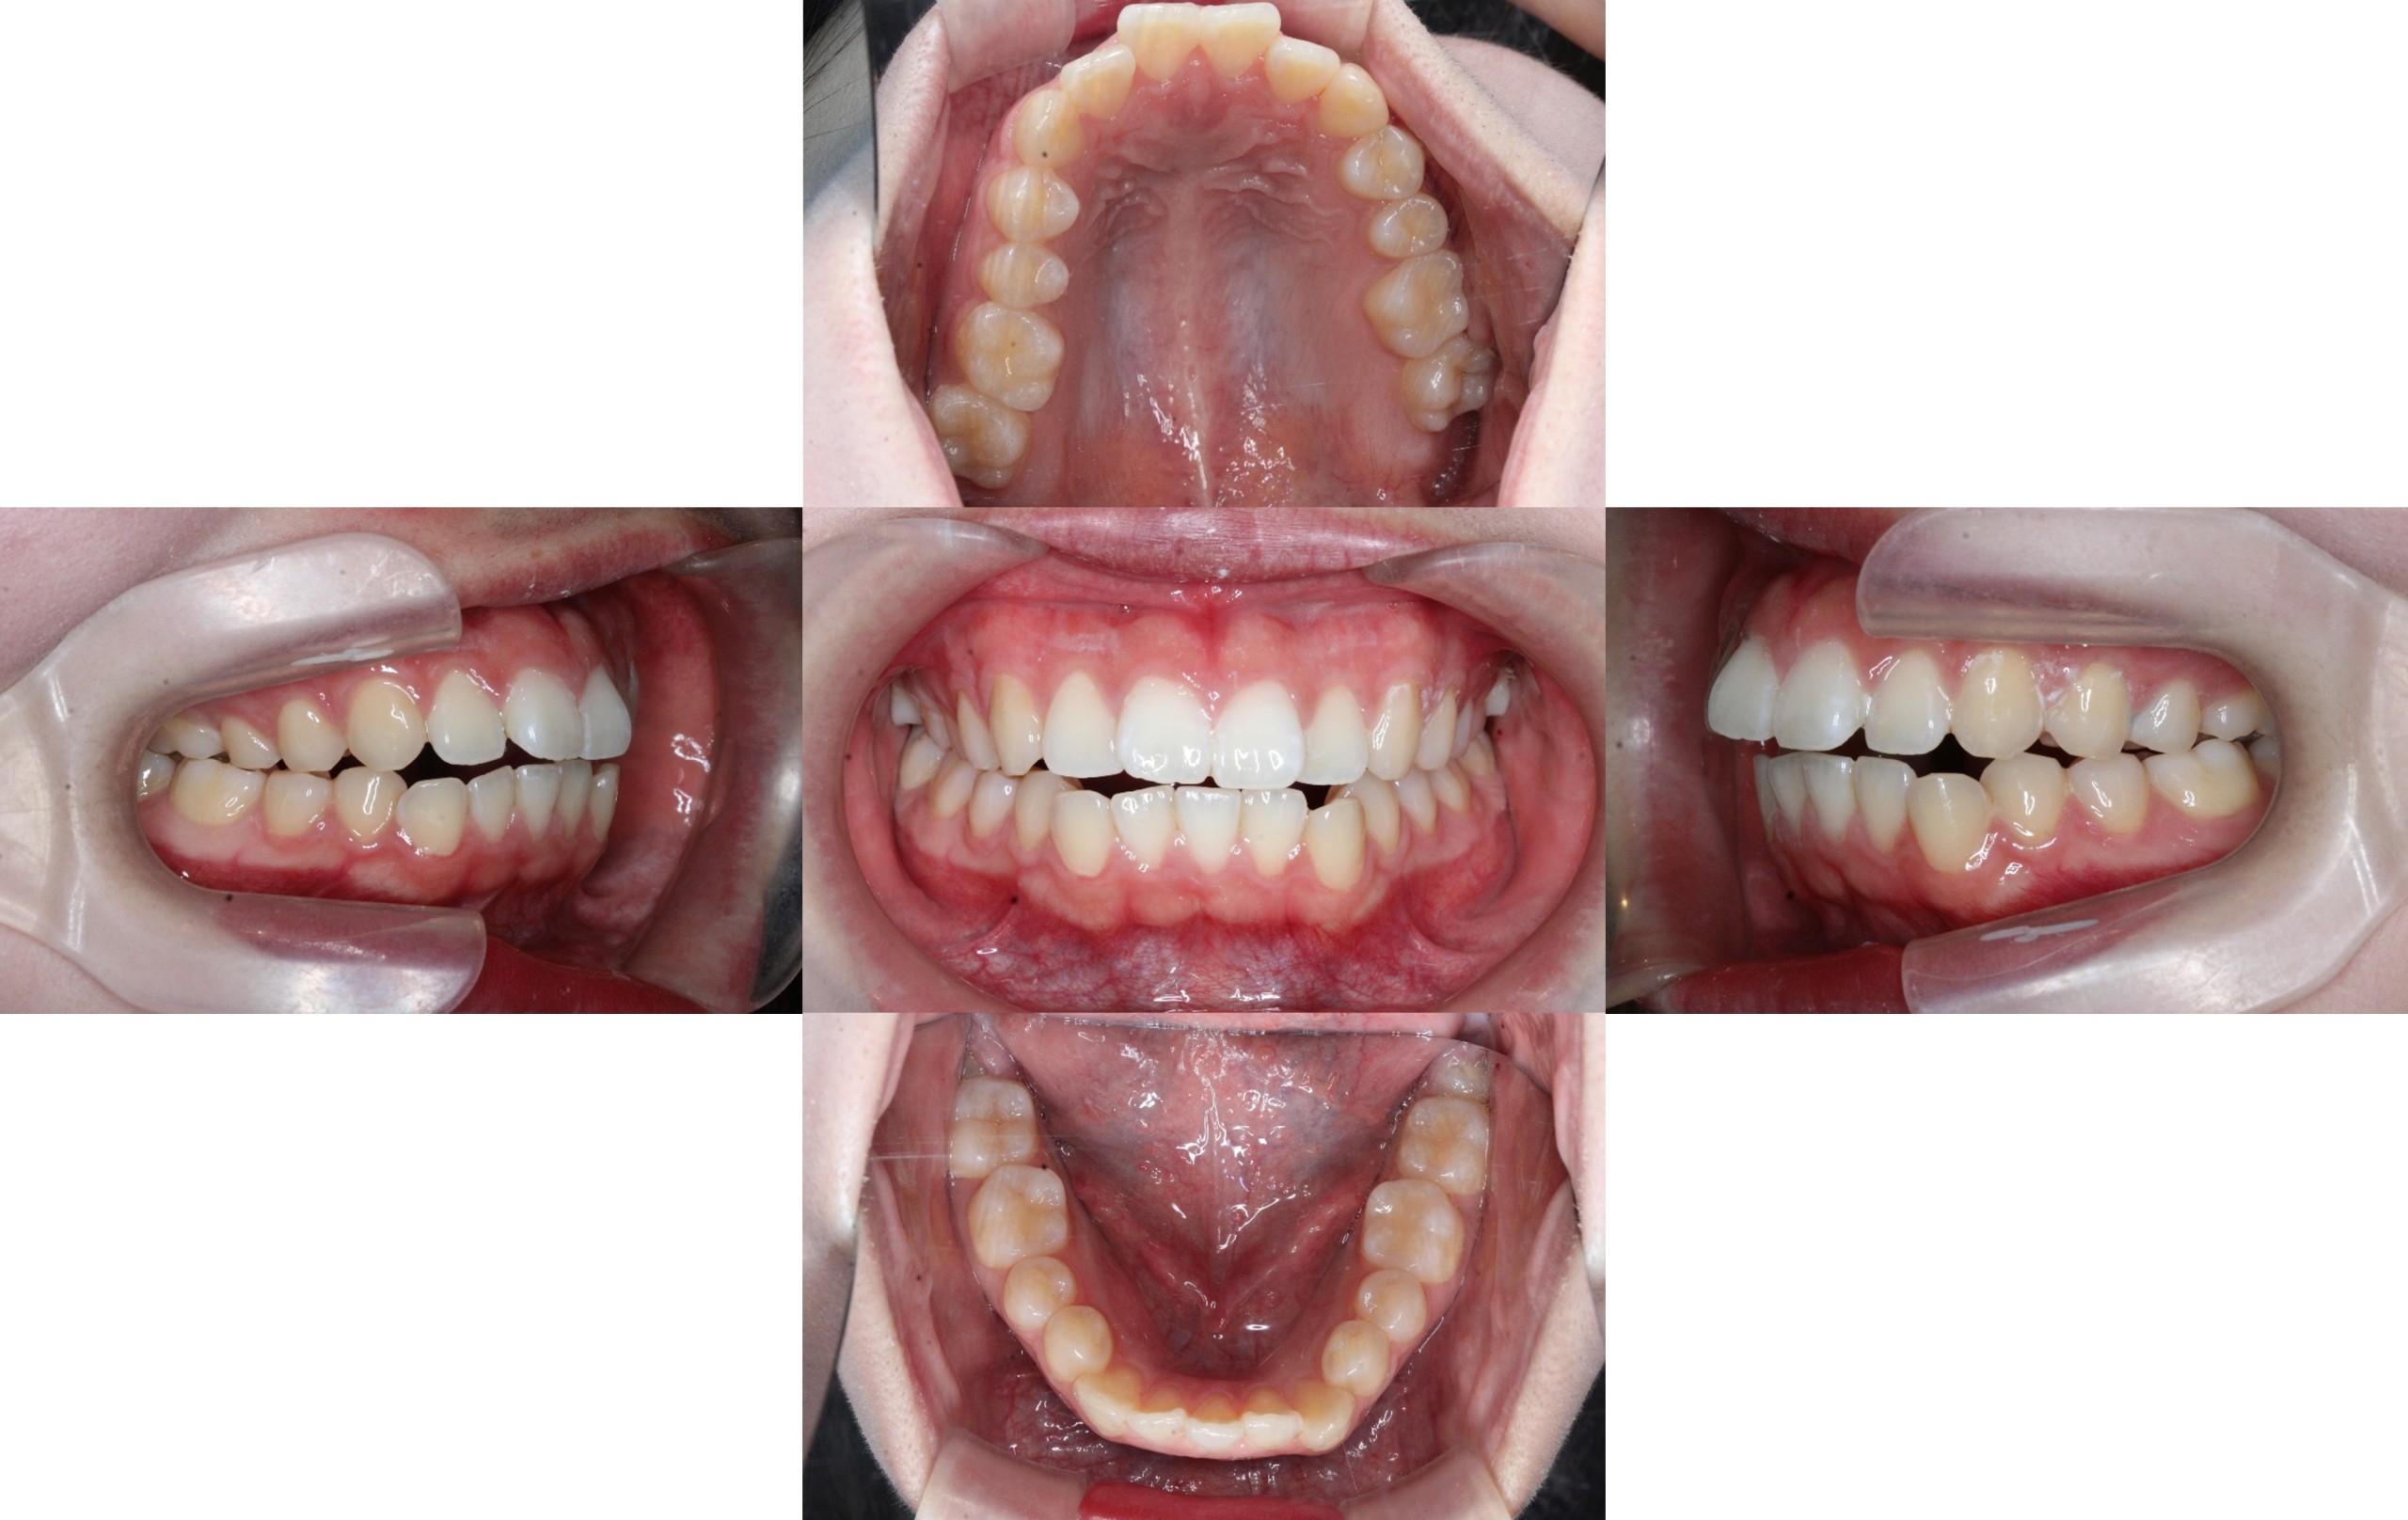

Before

初診